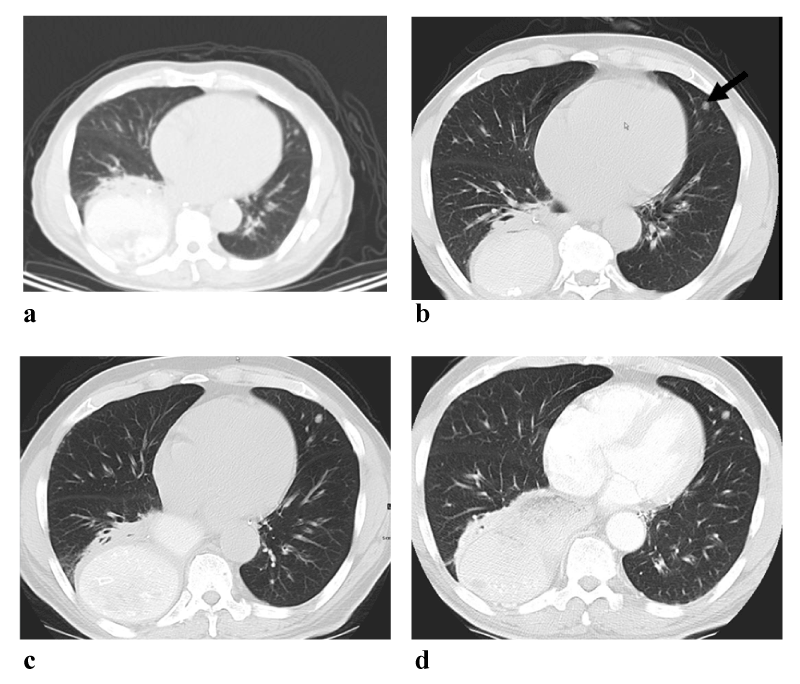

| Figure 1: a. A 0.6 cm pulmonary nodule (arrow) on NBH CT (from PET/ CT) in the left upper lobe which was missed by the radiologist. b. The radiologist identified the missed micronodule in the left upper lobe on BH CT chest (performed within 30 days of the NBH CT). c. Follow-up BH CT chest performed two years later shows mild increased in size of the left upper lobe nodule which measured 0.8 cm. d. Further follow-up BH CT chest performed 5 years later (from original NBH CT) showed the left upper lobe nodule to be stable and benign by imaging follow-up. |